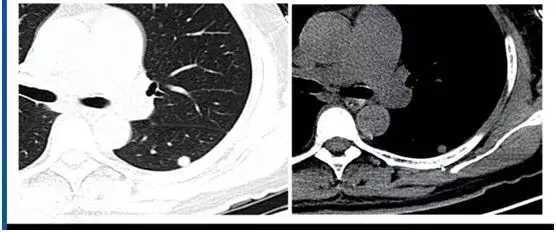

10. 真菌

真菌不同时期表现不同,有晕征 、支气管充气征、新月征、胸膜牵拉等可能表现。

隐球菌作为常见的真菌感染,易误诊为肺癌,影像表现为胸膜下带有晕征的小结节,三维重建后呈球形,单个结节诊断较为困难。隐球菌出现空洞时,空洞位于中央,可存在分隔,诊断时需要参考实验室检查结果。

1599963626251_b9559d65j00qgk3gj000td200lt0097g00g2006r.jpg

图13 隐球菌

隐球菌感染范围扩大形成实变后,治疗前后影像表现会有明显变化。

1599963701966_b88b5363j00qgk3gj000md200lo006hg00g2004s.jpg

图14 隐球菌实变治疗前后对比